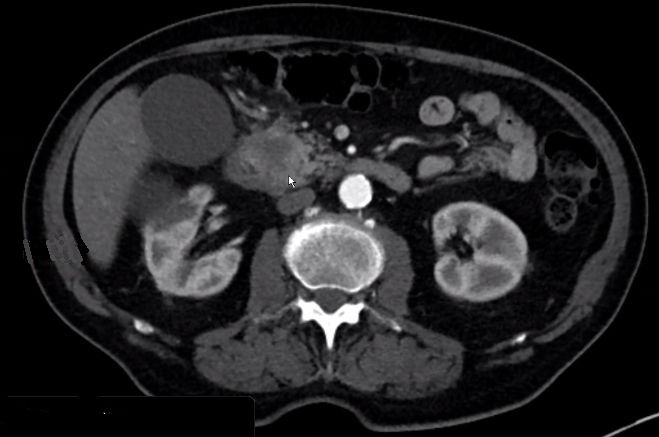

| V. mesenterica superior | 69-jährige Frau mit Pankreaskopfkarzinom. Das CT zeigt eine Infiltration der Vena mesenterica superior.

Nach Laparotomie inoperabel. Infiltrate an der Mesenterialwurzel. Bilidigestive Anastomose, Gastrojejunostomie, Cholezystektomie.![]() | |